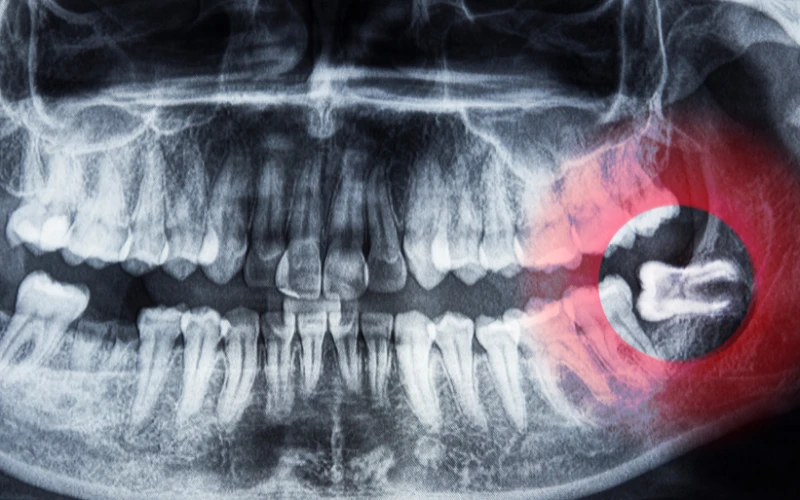

How Early Can X-Rays Detect Wisdom Teeth Growth?

Wisdom teeth development can be identified by dental X-rays at the age of 10–12. A panoramic X-ray may show wisdom tooth buds at this stage.

X-rays are critical tools for assessing the presence, placement, and development of wisdom teeth. To check tooth growth and angulation, dentists suggest panoramic or periapical X-rays. These images let dentists assess wisdom tooth size, position, and orientation before they emerge.